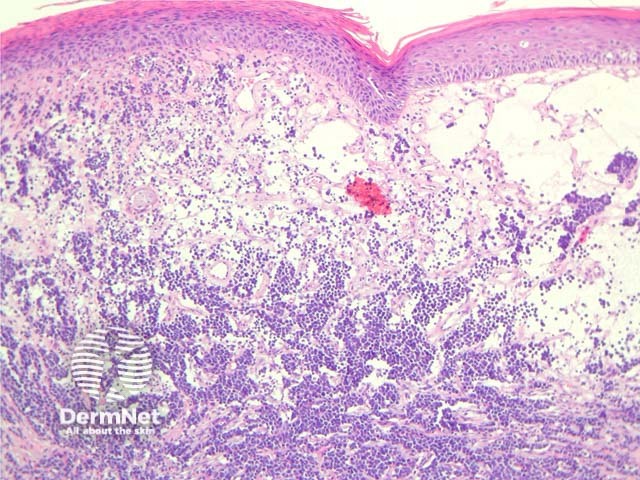

Merkel cell carcinoma is a neuroendocrine carcinoma composed of densely blue cells. The tumour is centered in the dermis with frequent involvement of the overlying epidermis (figures 1, 2) and may invade the subcutaneous fat. The tumour forms sheets, nests and rarely ribbons. The outlines of the cells often mold together or resemble lymphocytes (figures 3, 4). There are numerous mitoses, and there may be necrosis. Lymphovascular invasion is common.

Figure 1

Figure 2